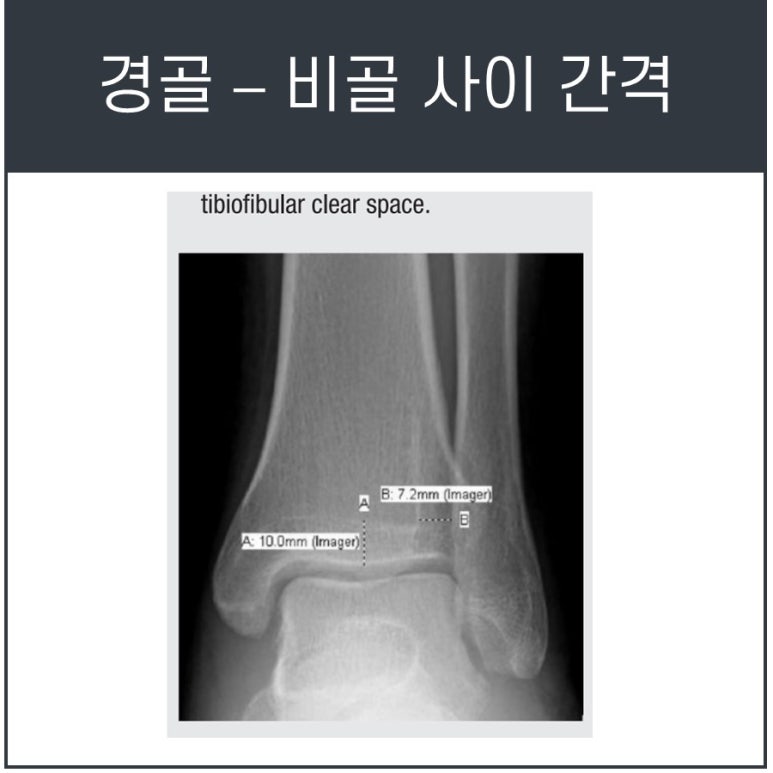

Ankle AP/Mortise view에서 경비관절의 연골성 부위인 clear space는 4-6mm가 정상입니다.

하지만 경비관절의 인대결합이 파열되면 해당 부위가 6~10mm이상으로 벌어집니다. 간접적으로 인대 파열을 추정할 수가 있죠.

이러한 이상소견이 보인다면 MRI 검사를 통해 반드시 파열 정도를 확인해보는 것이 좋습니다.